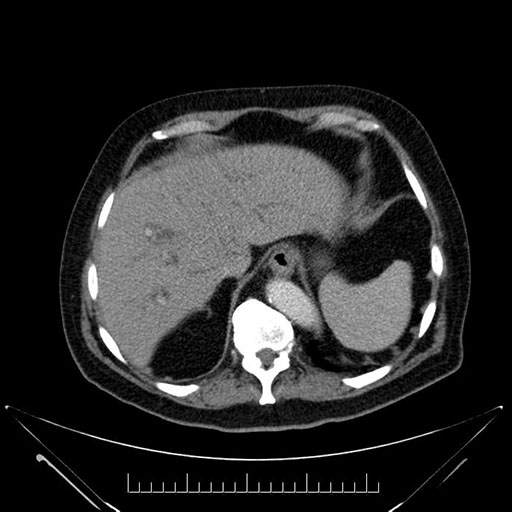

Imaging Analysis

Look through the patient's CT scan to identify any areas of concern for the necessary procedure.

Based on your CT findings, which issue(s) would give reason for "planned slowing down moment(s)" in this case?